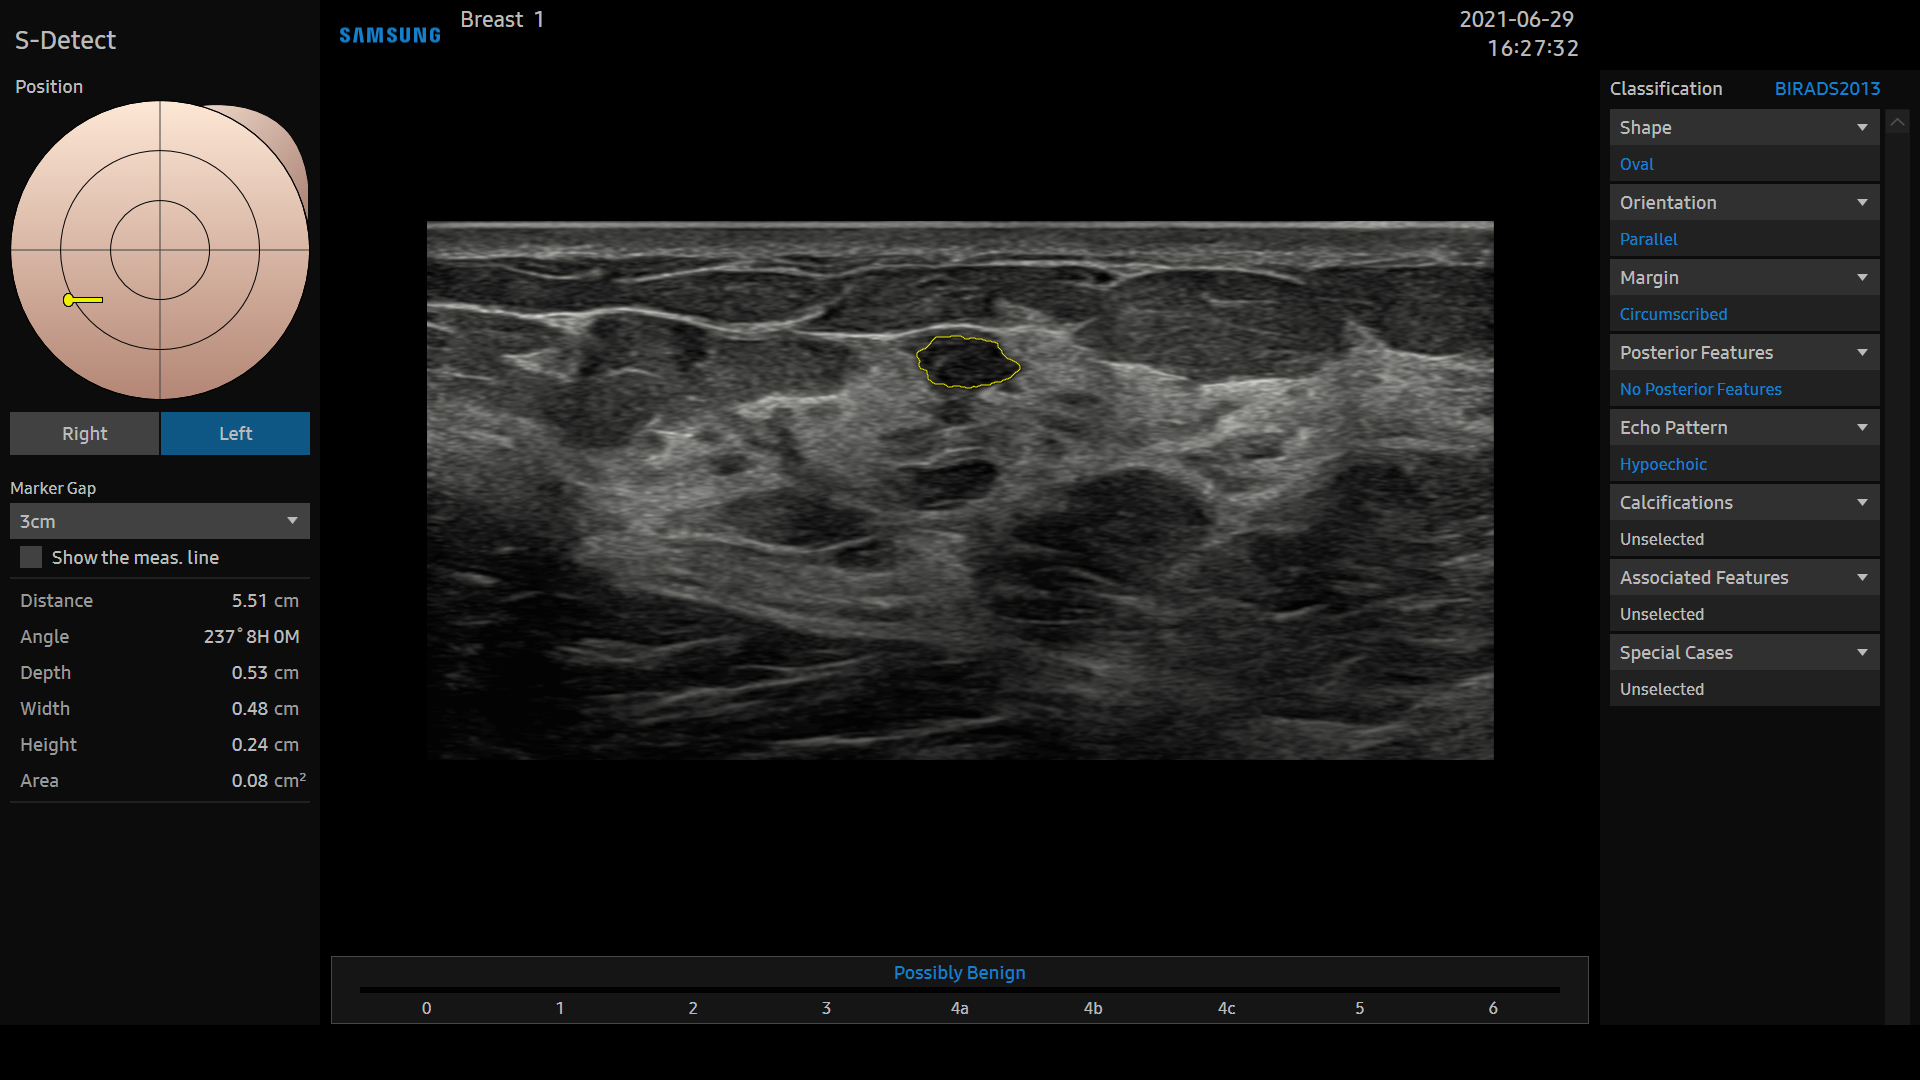

S-Detect™ for Breast est un outil d’intelligence artificielle qui analyse et catégorise les lésions détectées sur le sein en s’appuyant sur le système BI-RADS® ATLAS* (Breast Imaging Reporting and Data System [système de données et de comptes rendus d’imagerie mammaire], Atlas) pour établir des rapports standardisés.

* Marque déposée de l’American College of Radiology (ACR). Tous droits réservés.